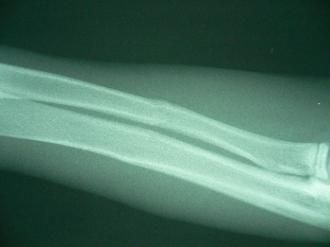

やんちゃ盛りの「いん」は、他の仲間と大騒ぎの毎日です。この度、仲間と遊んでいる最中に腰の高さから落ちたそうです。それ以降、足を痛そうにしているとの主訴で来院されました。病院で早速レントゲンを撮影すると、右の写真の通り、右前肢2本(前肢は、二本の骨で構成されます)の骨折が見られました!みずみずしい木の枝を折ったときの様相を呈するこの不完全骨折を「若木骨折」と呼びます。